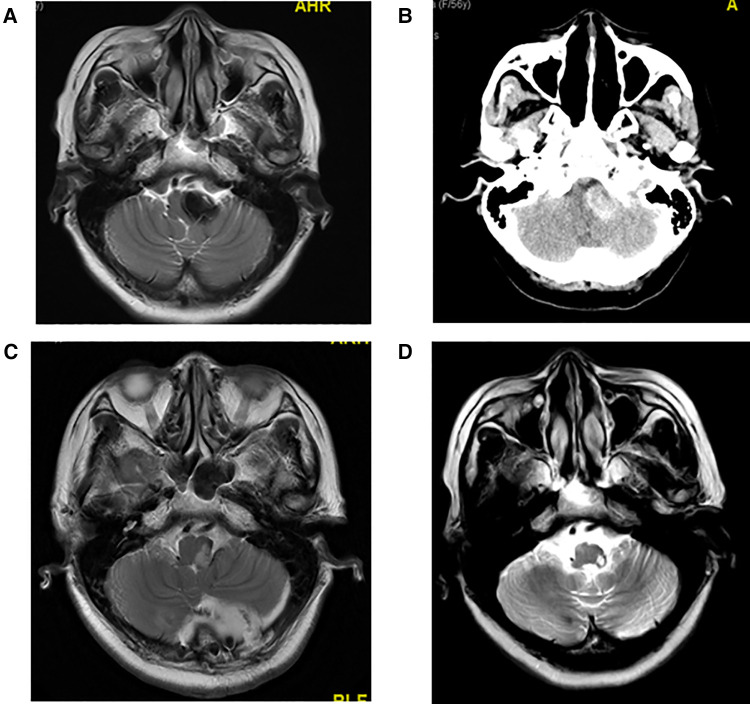

The maximum diameter of intracranial arachnoid cysts in group A was 6.38 cm on average, and that in group B was 2.97 cm on average, which was significantly different between the two groups (Tables 1, 4). In group A, all of the patients' intracranial arachnoid cysts showed a remarkable reduction in cyst size during the follow-up period (e.g., No. 6 and No. 5 patients' MRI images are shown in Figures 1E–H). However, two patients' cysts recurred, and an intracranial arachnoid cyst-peritoneal shunt was performed. In group B, patients' intracranial arachnoid cysts were resected, then the brain tissue tends to return to the normal anatomical structure (e.g., No. 13 patient's MRI and CT images are shown in Figure 3), and the cyst did not recur during the follow-up period.

Figure 3.

(A) Preoperative T2 MRI image of No. 13 patient. (B) Preoperative CT image of No. 13 patient with high CT signal. Hemorrhage was observed in the arachnoid cyst during craniotomy. (C) T2 MRI image of No. 13 patient at 1 week after craniotomy. (D) T2 MRI image of No. 13 patient at 1 year and 10 months after craniotomy.

It is still controversial which surgical approach is suitable for adult intracranial arachnoid cysts patients (9, 11). In the current study, we did not use the volume to compare the intracranial arachnoid cyst because in some cases the lesion shape was irregular and the area could not be calculated; thus, we used the maximum diameter of the lesion to compare the lesions. The maximum diameter of intracranial arachnoid cysts in group A is significantly larger than in group B. A large intracranial arachnoid cysts may have a wide range of adhesion with normal brain tissue, and resection might cause more serious postoperative complications; thus, in our study, neuroendoscopic surgery was applied to patient with larger intracranial arachnoid cysts (maximum diameter > 4.5 cm), and craniotomy was used to treat patient with small intracranial arachnoid cysts (maximum diameter < 3.0 cm). The selection of the surgical approach to the cyst with maximum diameter between 3.0 and 4.5 cm, depending on the cyst's the position, was close to the function area. For example, patient No. 7 had the lesion in motor function area, and neuroendoscopic surgery was performed to avoid motor function impairment (Figures 4A,B). No. 11 patient had the cyst in the dorsal part of the cerebellum, and craniotomy was used to complete resection of the lesion (Figures 4C,D).

Figure 4.

(A) Preoperative T2 MRI image of No. 7 patient. (B) CT image of No. 7 patient at 1 month after neuroendoscopic surgery. (C) Preoperative T1 MRI image of No. 11 patient. (D) T1 MRI image of No. 11 patient at 1 week after craniotomy.